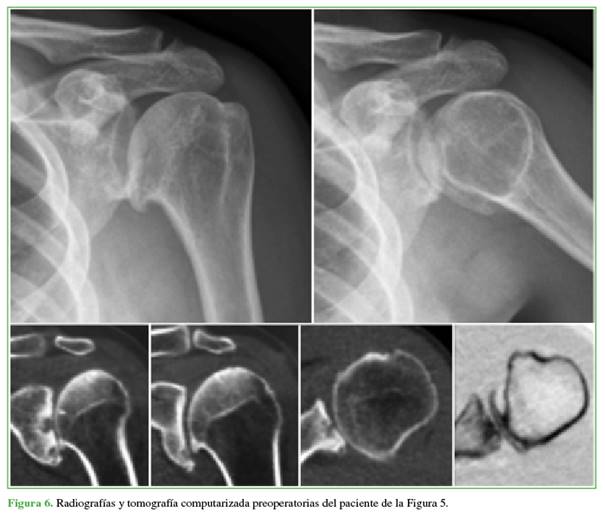

Resultados radiográficos: antes de la cirugía, los 25 hombros tenían artrosis grado 3 de la clasificación de Samilson y Prieto12 (pérdida de luz articular, quistes y osteofitos) (Figuras 6 y 7).

Hubo 7 casos de desgaste asimétrico de la glenoides (4 tipo B1 y 3 tipo B2 de Walch13). Además, 7 hombros tenían una subluxación moderada y 1, una severa. Tras la cirugía, la subluxación se resolvió en 22 hombros y persistió levemente en 3 pacientes. El espacio articular glenohumeral promedio aumentó de 1,2 mm (rango 0-3) antes de la operación a 3,4 mm (rango 1-5) después. La TC de control reveló una disminución del espacio articular por desgaste del alomenisco, correlacionado con el tiempo de evolución (Figura 8). Para una evaluación más detallada de la erosión glenoidea posoperatoria, se analizaron las TC de seguimiento en el último control. Se clasificó la erosión glenoidea de la siguiente manera: 15 pacientes (60%) tenían erosión mínima o nula; 7 (28%), erosión moderada y 3 (12%), erosión severa. Estos hallazgos cualitativos confirman la progresión del desgaste glenoideo a largo plazo, a pesar de la interposición meniscal, la erosión fue una complicación esperada. En cuanto a los hallazgos intraoperatorios relevantes, en 2 pacientes con antecedentes de luxofractura de húmero, se reparó el manguito rotador con puntos de suturas no reabsorbibles. Uno de ellos tenía una lesión del supraespinoso y otro, del subescapular. Cinco tenían cuerpos libres articulares en cantidad variable.1-3 No se registraron infecciones. Se observó un hematoma posoperatorio no complicado en un paciente y un resultado funcional pobre, pero con franca mejoría del dolor en una mujer con antecedente de osteonecrosis por luxofractura de húmero.